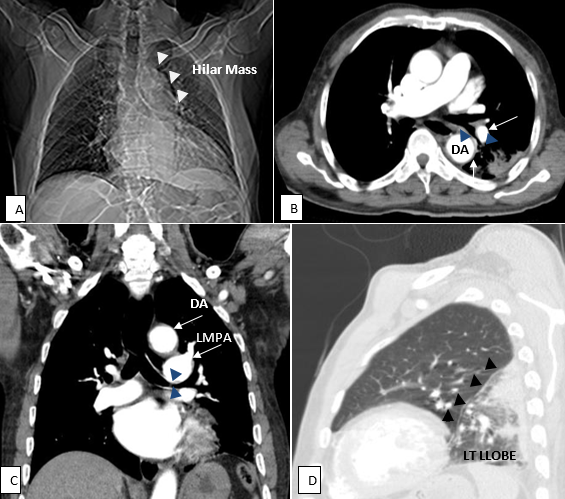

Aortic and left pulmonary artery dilatation: an unusual cause of a left hilar mass and lung collapse

An 80 year old clergy, presented with a 5-day history of left-sided chest pain which was non-radiating but had cough productive of white sputum. No history of haemoptysis, dyspnoea, orthopnoea or paroxysmal nocturnal dyspnoea was elicited. However, a history of smoking 2 cigarettes per day for 10 years was present. He is a known hypertensive on medications,also being managed for diverticulosis and Benign Prostatic Hypertrophy.Respiratory rate was 26cycles per minute with crepitations in the left mid-and lower lung zones. Bilateral pedal oedema was found but the cardiovascular and gastrointestinal systems were normal. Requests for an ultrasound, a chest X-rayCXR and Contrast Enhanced computerised tomography CECT of the chest were made. High resolution CECT of the chest was performed with a 64-slice Toshiba CT. Multiplanar images in axial, coronal and sagittal planes were acquired at 1mm cuts in pre-and post-contrast series. Images depicting the abnormality are shown (A, B, C,D). No further invasive workup like a biopsy was indicated following imaging. Prior to the CECT, bronchogenic CA was considered in view of the long standing smoking history. The role of Computerised tomography in the evaluation of chest symptoms has been emphasised in these images.